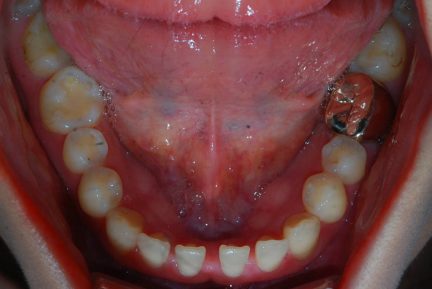

Classe III, articulé postérieur, arcades étroites, arcades asymétriques, déviation de la ligne médiane mandibulaire, décalage de la ligne médiane, rotations, espacement

- Une expansion précédente du maxillaire a été effectuée.

- Après l'expansion, ce cas a été préparé pour la chirurgie orthognatique.

- Seul Invisalign sans autre appareil et sans besoin d'élastiques a été utilisé pour la préparation.

- Une surcorrection de l'articulé croisé postérieur a été planifiée pour s'assurer que nous n'aurions pas de contacts prématurés dans la période postopératoire immédiate.

- Entre 3,4 et 3,5, nous n'avons fait qu'une réduction interproximale de 0,3mm pour renforcer la fermeture des espaces.

- La petite déviation médiane a été corrigée avec des aligners supplémentaires.

- La dent 1,7 a été extraite car elle n'avait pas d'antagoniste et le patient ne souhaitait pas poser d'implant dans la région de 4,7

État initial